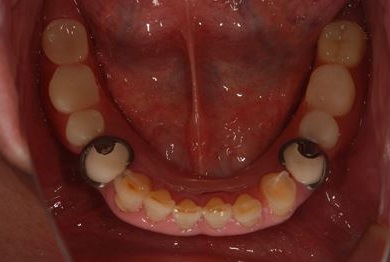

インプラントの症例写真 IMPLANT

骨再生スピードインプラント治療+セラミック治療

| 治療内容 | インプラント4本(ソケットリフト・抜歯即日)、テンポラリーインプラント2本、メタルボンドクラウン9本 | ||||||||||||||||||||||||||||||||

| 総治療費 | 2,025,975円 | ||||||||||||||||||||||||||||||||

| 治療期間 | 1年9ヶ月 |